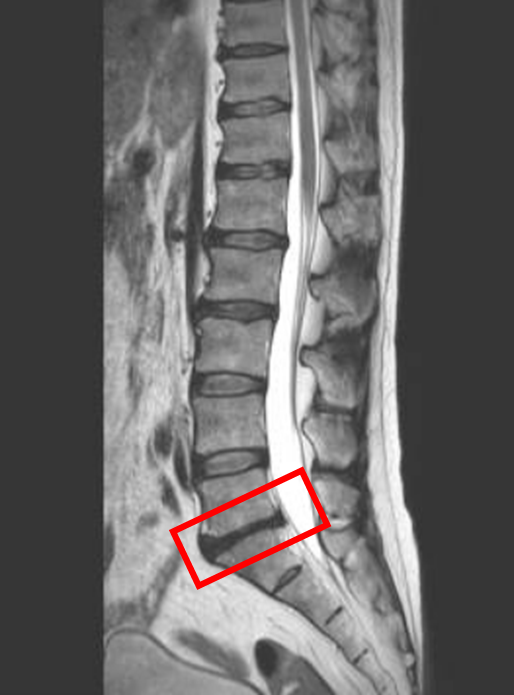

この患者様は赤い枠で示されている箇所(L5/s)に椎間板変性症を認めます。